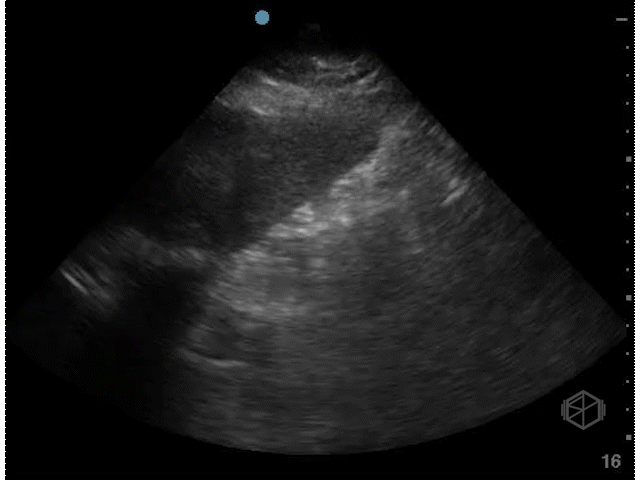

The next SonoProp goes to Dr. Frances Rusnack and Dr. Vivek Sharma. They scanned a ~60-year-old female with no reported past medical history who had right upper quadrant pain for 3 days and saw the following:

This is a great gallbladder scan that demonstrates acute cholecystitis. There is notable gallbladder wall thickening, pericholecystic fluid, and a hydropic gallbladder that is highlighted very well here.

CT of the same patient showing significantly distended/hydropic gallbladder with pericholecystic fluid.

• A hydropic gallbladder (in adults) is one that measures over 10x5cm, it is one of the six signs of potential cholecystitis. There is no one sign that will ultimately definitively diagnose cholecystitis, but multiple signs together with clinical correlation help make the diagnosis.

• A wider gallbladder (>5cm) is considered worse than an elongated one and portends a higher complication rate such as necrosis.

• This patient’s gallbladder was longer than 11x~6.5cm, significantly hydropic. The operative note mentioned that the gallbladder was acutely edematous with pericholecystic fluid and necrosis of part of the anterior wall of the gallbladder. There were multiple large impacted stones in the gallbladder that required widening the extraction site incision.